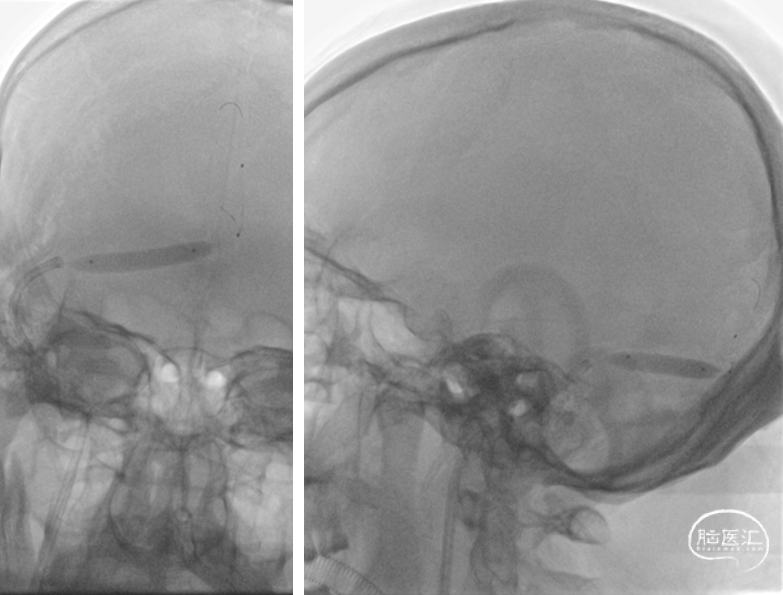

术后复查头颅CT(2022-1-15)

术后患者情况:

患者头痛消失,无不适主诉

1月21日复查腰椎穿刺,脑脊液压力230mmH20